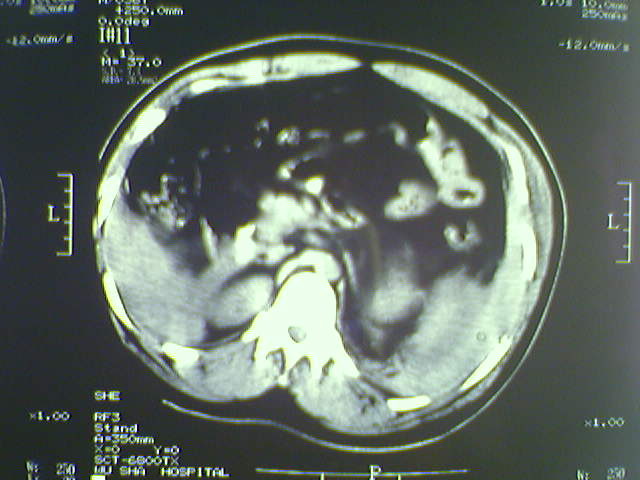

以下是引用lxq2000在2008-6-3 22:28:00的发言:[br]腹腔积液,腹壁软组织及左侧腰大肌肿胀建议mr检查。

以下是引用zjzjr在2008-6-3 21:01:00的发言:[br]腹腔积液+邻近软组织肿厚.考虑感染性病变可能性大.